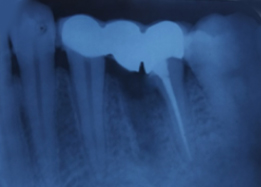

Prosthesis Cementation (Bridge)

Hemisectomy

Radiograph with Prosthesis (8 Months)

Powered By - www.calcuttayellowpages.com